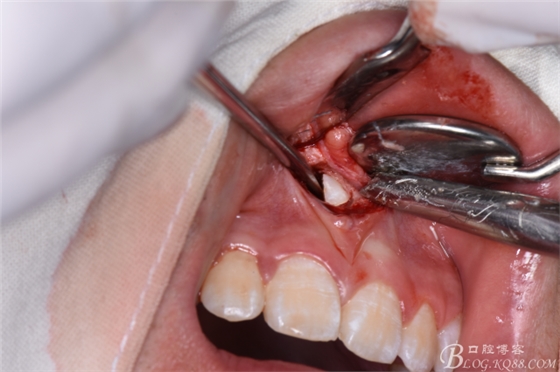

圖11.暴露出整個多生牙牙冠

圖12.將暴露多生牙牙冠分成牙根河牙冠兩部分

圖13.取出多生牙牙冠